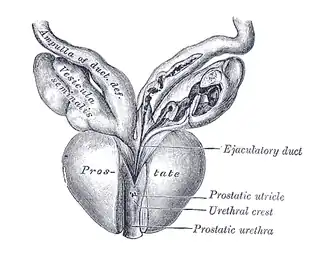

Die Prostata liegt subperitoneal, das heißt unter (bei Tieren entsprechend hinter) dem Bauchfell. Sie ruht auf dem Diaphragma urogenitale und schmiegt sich von kaudal (beim Menschen unten, bei Vierfüßern hinten) an den Hals der Harnblase an. Dorsal (zum Rücken hin) wird sie durch den Mastdarm begrenzt, ventral (zum Bauch hin) durch die Schambeinfuge. Mit dieser ist sie durch ein Band, das Ligamentum puboprostaticum, verbunden. Durch die Mitte der Prostata verläuft die Harnröhre. Aus diesem Grund kann es bei einer krankhaften Vergrößerung der Prostata zu Problemen beim Wasserlassen bis hin zum Blasenverschluss kommen.

Anatomisch lässt sich die Prostata in einen rechten, linken und mittleren Lappen untergliedern: Lobus prostatae dexter, Lobus prostatae sinister und Isthmus prostatae (Lobus medius). Die funktionelle Gliederung in Zonen nach McNeal unterscheidet die periurethrale Zone (um die Harnröhre herum), die Transitionalzone (Übergangszone), die zentrale Prostatazone (Innenzone), die periphere Prostatazone (Außenzone) und die drüsenfreie vordere Prostatazone.[1]

Durch die Prostata verläuft beim Menschen außerdem der paarig angelegte Spritzkanal (lat. Ductus ejaculatorius), durch den während der Ejakulation ca. 70 % des Ejakulat-Volumens hindurchfließen, nämlich die Fraktionen aus dem gleichseitigen Nebenhoden und aus der gleichseitigen Bläschendrüse.[2]

Der Querschnitt der Prostata kann in drei Zonen unterteilt werden, die sich in den Ausführungsgängen der Drüsen unterscheiden: die periurethrale Mantelzone, die Innenzone und die Außenzone. Die Ausführungsgänge der Drüsen in der inneren Zone enden direkt in die Harnröhre. Die Drüsen in der äußeren Zone sammeln ihr Sekret in gemeinsamen Ausführungsgängen, bevor sie in der Harnröhre enden. Diese Einteilung ist bei der Entstehung von Tumoren von Bedeutung (s. unten).

Die Ausführungsgänge (Ductuli prostatici) der Prostatadrüsen in der Prostata münden im Sinus prostaticus beidseits des Colliculus seminalis (Samenhügel) der Harnröhre. Ihr Drüsenepithel ist funktionsabhängig entweder einschichtiges Plattenepithel oder mehrreihiges hochprismatisches Epithel. Der Hohlraum (Lumen) der Drüsen enthält Concretio prostatica, konzentriertes geschichtetes Sekret.